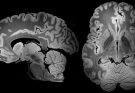

Por Dentro do Cérebro

Imagem de capa: captura de tela de cena de um dos vídeos. Imagens incríveis do Cérebro Humano Idoso e Saudável Estes vídeos foram gerados com imagens de escaneamento por ressonância …